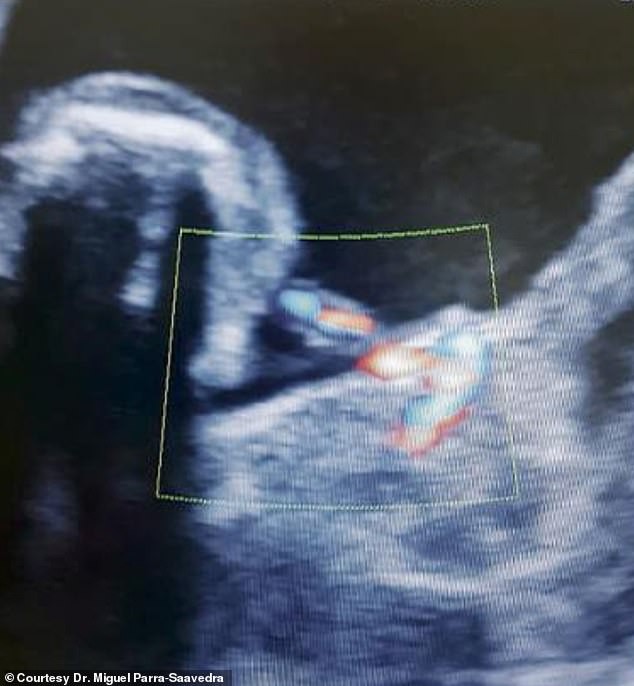

Bức ảnh siêu âm ở tuần thứ 35 cho thấy một thai nhi khác đang phát triển trong bụng bé Itzamara

Khi sử dụng máy siêu âm màu với chức năng hiển thị hình ảnh đa màu của mạch máu ở cấp độ cực kỳ chi tiết, Tiến sĩ Parra-Saavedra đã phát hiện một thai nhi bé xíu khác với dây rốn của riêng mình chứ không phải nang gan. Ông vô cùng kinh ngạc khi được tận mắt chứng kiến trường hợp "thai trong thai" cực kỳ hiếm gặp này. Nhưng có lẽ mẹ bé, cô Monica mới là người sốc nhất.